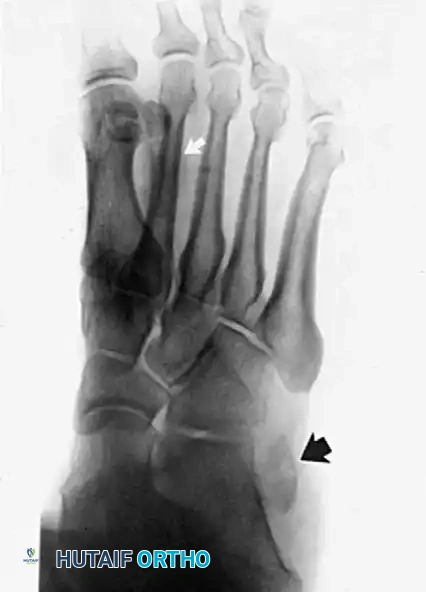

- Plain Radiographs: Weight-bearing anteroposterior, lateral, and mortise views of the ankle and foot are obtained to rule out fractures (e.g., "fleck sign" indicating SPR avulsion), os peroneum pathology, or varus hindfoot alignment.

Radiographic evaluation of the foot and lateral column.